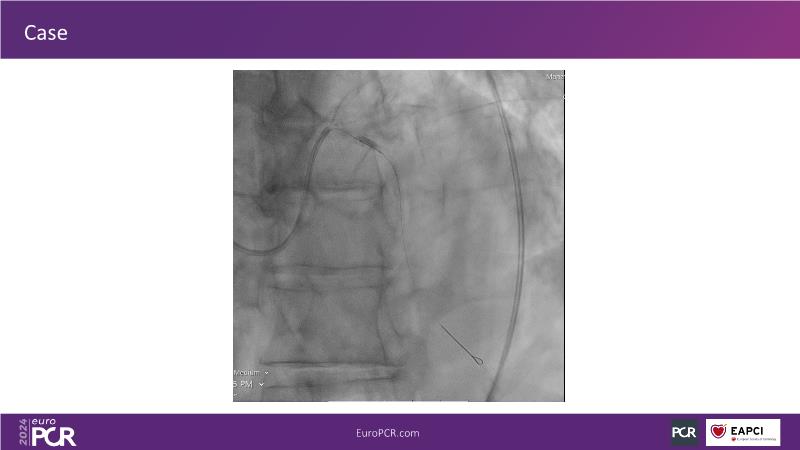

Tune into this 2024 session for insights into the latest ESC guidelines, strategies to prevent and treat no reflow, and an examination of trials like TASTE, TAPAS, and TOTAL on coronary thrombus management. Explore also the outcomes of the CHEETAH study, pondering a potential paradigm shift, and delve into a case study on thrombus removal in a patient with high thrombus burden.